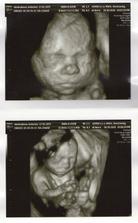

3D - nas poklad

Nas drobcek na 3D

bolo to teraz v nedelu 24.10 a bola som 22 tyzden 5 den.Ale mala je o tyzden popredu tak podla merania lekara bola 23 tyzden 5 den